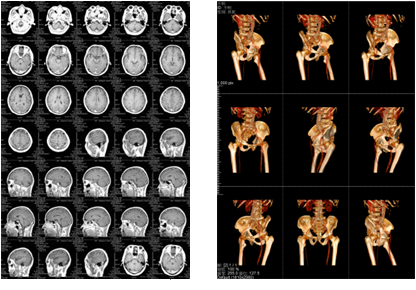

膠片紙輸出樣張示意